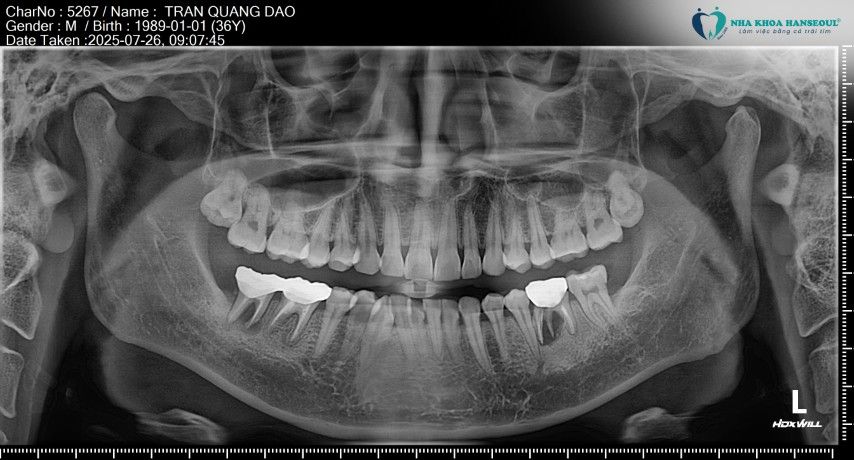

Theo chia sẻ của anh Đạo, cách đây vài năm, hai răng hàm 36 và 47 của anh từng bị sâu răng nặng, sâu đã ăn vào tủy. Khi đó, anh lựa chọn điều trị tủy và chụp răng sứ tại một nha khoa khác với mong muốn giữ lại răng thật để ăn nhai lâu dài.

“Lúc mới làm xong thì tôi thấy ăn nhai vẫn ổn, không đau nên cũng yên tâm,” anh Đạo kể lại. Tuy nhiên, sau một thời gian, vùng răng này bắt đầu xuất hiện ổ áp xe lớn, kèm theo cảm giác đau nhức và sưng, răng bị lung lay gây ảnh hưởng tới ăn uống và sinh hoạt. Khi đến thăm khám tại Hanseoul và chụp phim CT Cone Beam, Thạc sĩ, Bác sĩ Trần Việt Hà xác định tình trạng nhiễm trùng kéo dài đã khiến xương hàm quanh chân răng bị tiêu nghiêm trọng.

Theo bác sĩ Trần Việt Hà, trong những trường hợp răng đã nhiễm trùng nặng, kèm tiêu xương nhiều, việc tiếp tục giữ răng không còn ý nghĩa bảo tồn. Nếu không xử lý triệt để, ổ viêm có thể lan rộng, ảnh hưởng đến xương hàm và các răng kế cận.

Sau khi đánh giá tổng thể, bác sĩ Trần Việt Hà đã chỉ định nhổ 4 răng, bao gồm răng 36, 47 do nhiễm trùng nặng và răng khôn 18, 28 có nguy cơ gây viêm, đau và ảnh hưởng đến răng kế cận.

Với hai răng 36 và 47, bác sĩ tiến hành nhổ răng kết hợp nạo sạch ổ áp xe, làm sạch mô viêm và kiểm soát nhiễm trùng bằng kháng sinh phù hợp. Đây là bước quan trọng nhằm loại bỏ hoàn toàn vi khuẩn trước khi tiến hành cấy implant, giúp hạn chế tối đa nguy cơ biến chứng về sau.